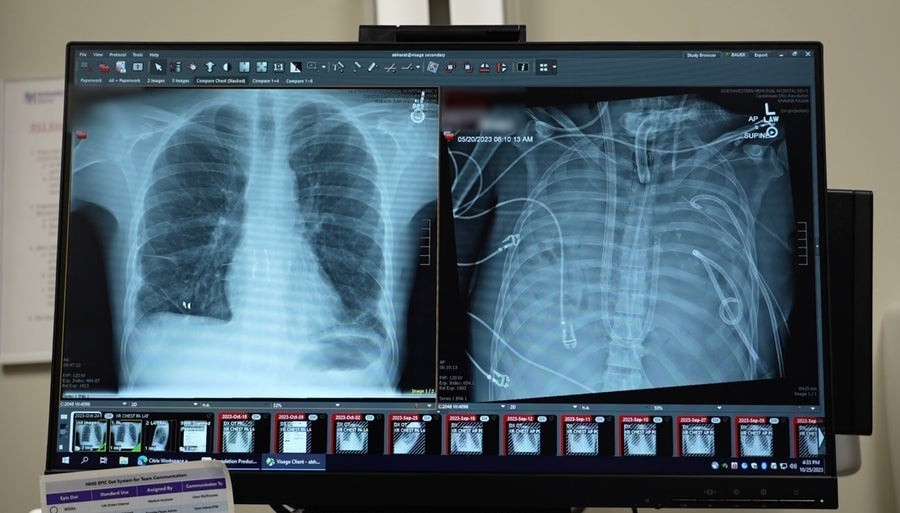

lungs.jpg

Οι ακτινογραφίες δείχνουν τους νέους πνεύμονες (αριστερά) και τους παλιούς πνεύμονες (δεξιά) του33χρονου ασθενούς